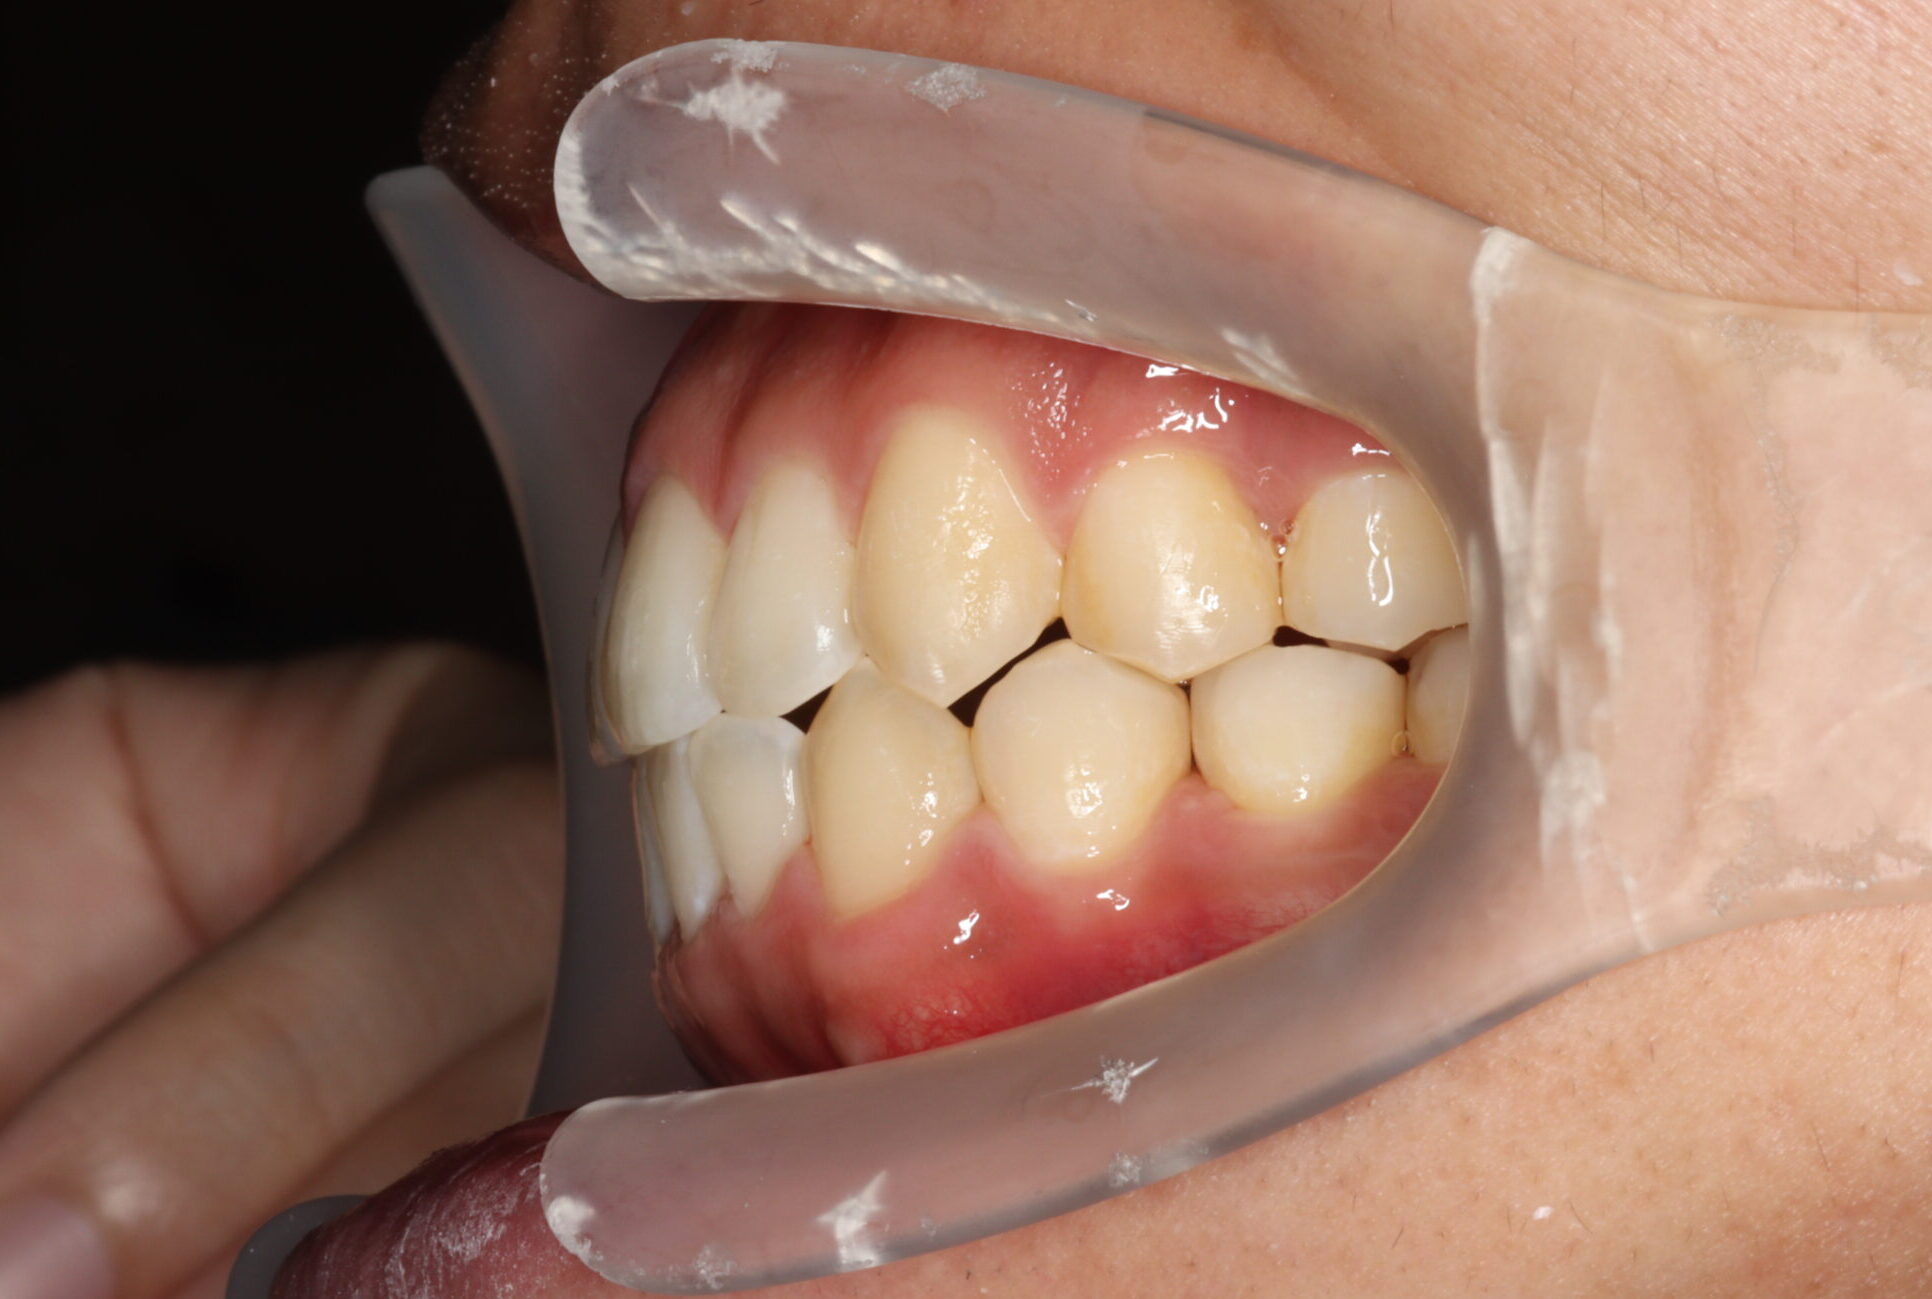

24歳男性 1年11ヵ月

24歳 男性

【主訴】でこぼこ、上下の歯が噛まない

【診断】開咬、叢生(でこぼこ)、上下顎前歯唇側傾斜、舌突出癖

【治療方法】マルチブラケット装置にて排列を行う。咬合の確立のため顎間ゴムを併用し、舌突出癖の改善のため筋機能療法を行う